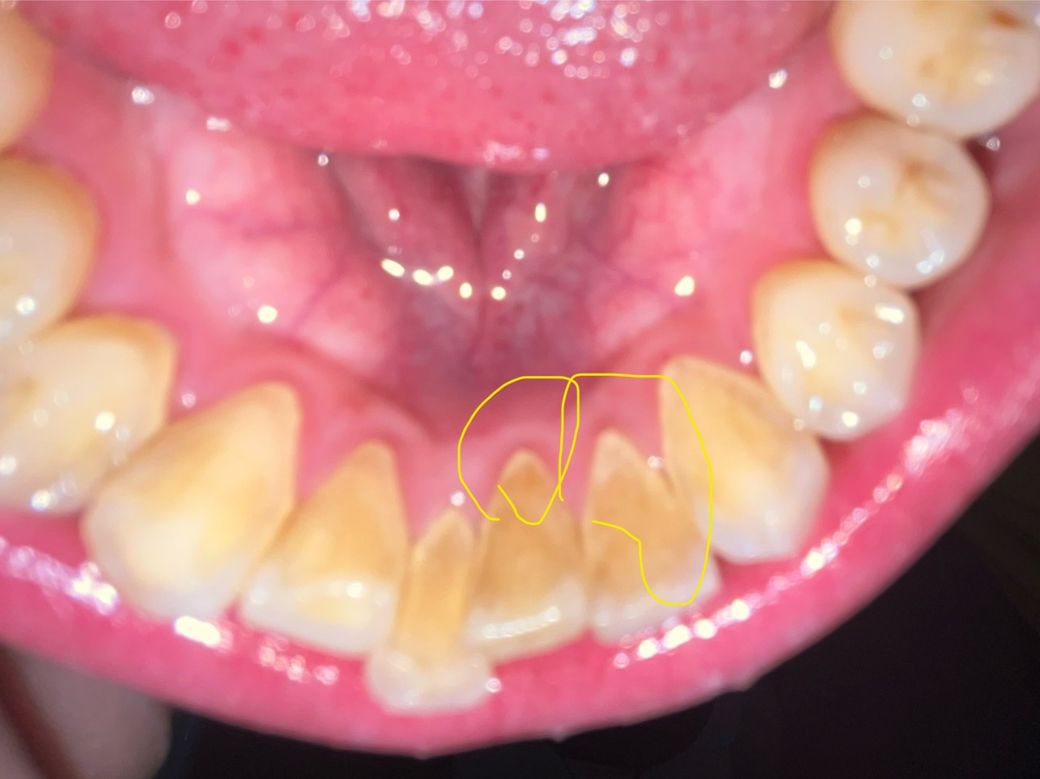

안녕하세요 어제 스케일링을 받았는데 사진상 노란 색으로 동그라미 친 부분에 치석이 있어보이는데 이게 치석이 남아있는건가요? 아니면 다른건가요? 잇몸과 인접면에 희게 있어요 닦아도 안없어져요

• 1번 째 사진

이틀전이라면 치석이 남아 있다고 보는 것이 맞습니다. 스케일링을 한 치과를 다시 한 번 방문해서 해당 부분에 대해서 말씀을 한 번 해보는 것이 좋습니다. 지금 상태에서는 남아 있다고 판단하는게 맞아 보입니다.

사진 상으로는 치석으로 보입니다. 일반 칫솔질로는 떨어지지는 않으며 스케일링 등 요하리라 보입니다.

치석이 좀 남아있는 것 같습니다 해당 부위는 워낙 치석이 많이 쌓이는 곳이라 스케일링 아주 꼼꼼히 한게 아니면 조금 남을 수도 있습니다

양치질로는 원래 치석 안떨어집니다